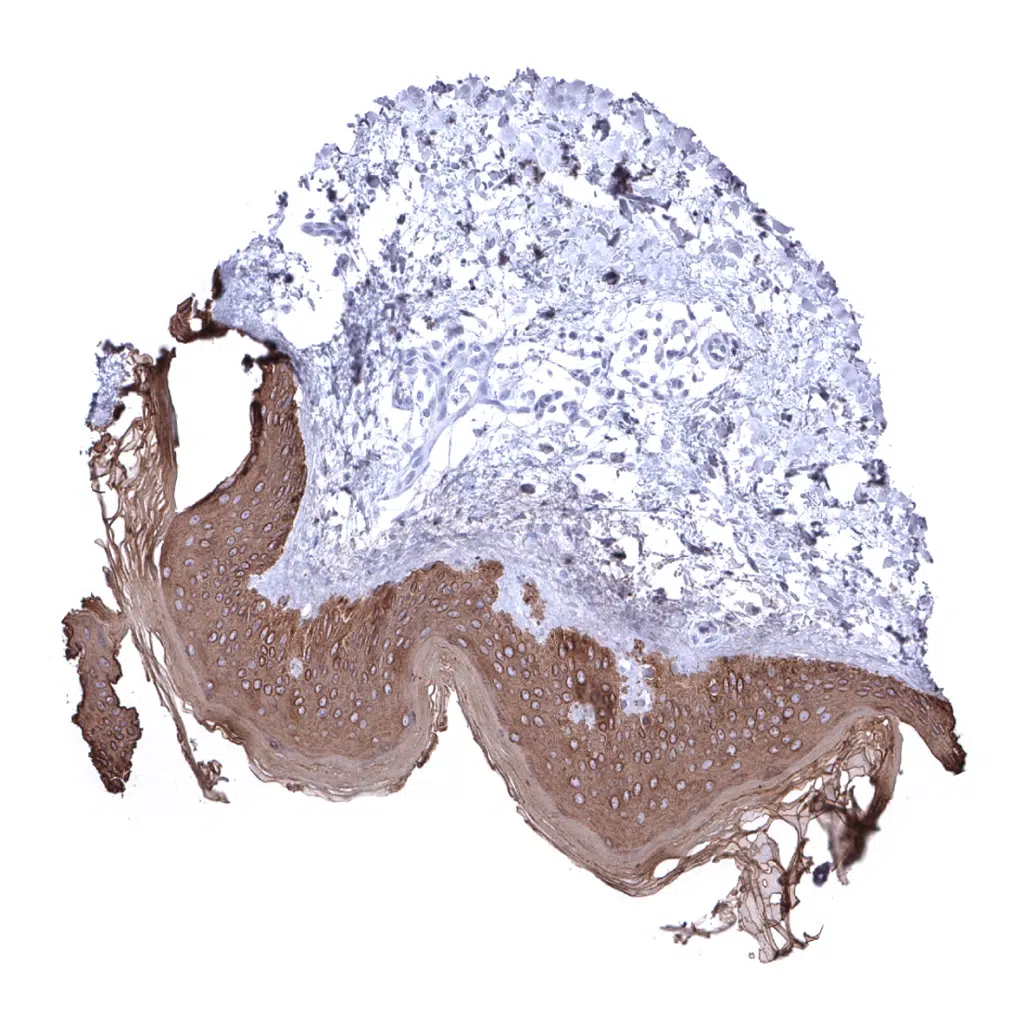

Tonsil, surface epithelium - Squamous epithelial cells are strongly pan Cytokeratin positive while all lymphocytes are pan Cytokeratin negative.

Tonsil - pan Cytokeratin stains all epithelial cells in the tonsil crypts.